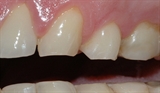

Et detaljbilde viser rette, slitte kanter på tennene.